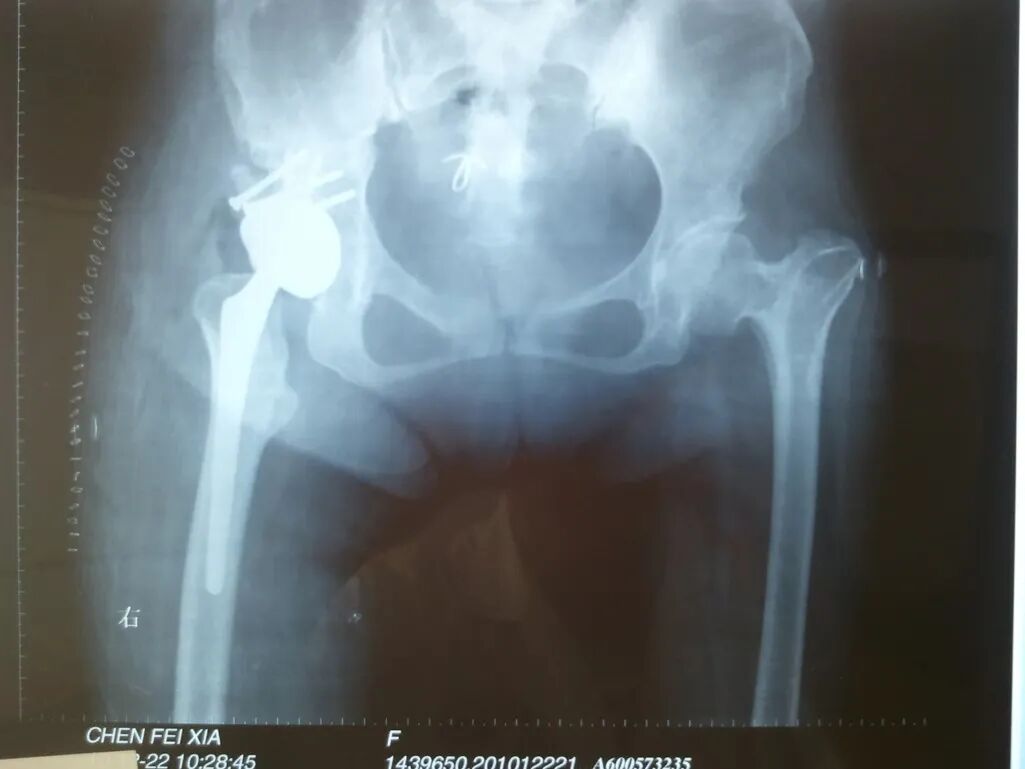

女性患者,48岁,右髋疼痛25年,加重1年

单看股骨侧,大转子顶点和股骨头旋转中心的关系恢复了

但髋臼旋转中心点上移了造成了患肢术后肢体短缩因此如果术中发现髋臼旋转中心点有上移或下移,股骨假体也应相应的吊高或下沉以获得双下肢等长

术后股骨头旋转中心点增高,导致患肢延长